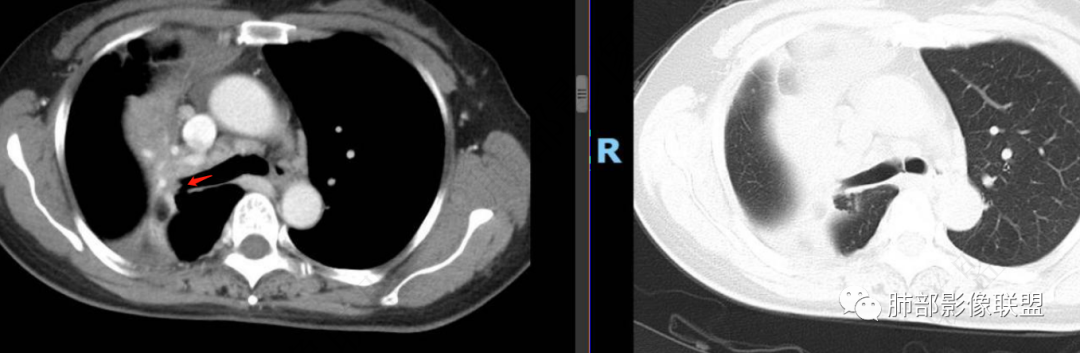

晨读病例,老年男性,乏力,纳差,近来发热,右肺上叶团片状阴影,内见空洞,空洞内壁不光滑,见短液平,增强病灶壁可见不均匀强化,似有边界不清晰的坏死,病灶周围可见片状模糊阴影,考虑恶性病变,鳞癌或腺癌伴感染。

老年男性,肺气肿背景,右肺较大分叶状肿块,密度不均,内坏死空洞形成,坏死区边界不规则,周围多发斑片蜂窝状、网格状高密度影,考虑鳞癌合并感染

右肺上叶及中叶不规则肿块伴周围模糊影,其内小叶间质结节样改变,肿块不均匀强化,坏死及空洞,坏死边界不清,血管显示尚可,考虑腺癌,鉴别淋巴瘤

老年男性,有咳嗽发热。右肺中上叶团状软组织肿块,周围磨玻璃渗出改变,病灶内密度不均,可见低密度坏死及空洞影,空洞内壁凹凸不平,近肺门侧可见明显大面积坏死。近端支气管堵塞不明显。考虑恶性肿瘤伴感染,腺癌?鉴别鳞癌,感染性病变。

右肺上叶团片状阴影,内见空洞,空洞内壁不光滑,偏心,,增强不均匀强化,内有边界不清晰的坏死,病灶周围可见片状模糊阴影,右下肺也有磨玻璃病灶,Crp高,腺癌

70岁男性,发烧病史,右肺巨大肿块,边缘分叶,内部空洞,洞内见附壁结节,局部支气管阻塞,肿块周围见大片阻塞性炎症;实验室检查,炎性指标增高;考虑恶性肿瘤伴阻塞性肺炎,鳞癌可能。

老年男性,乏力,纳差,发热。右肺上叶团片状阴影,密度不均,可见低密度坏死,坏死边界不清,可见空洞形成,见短液平;增强病灶呈不均匀强化,其内血管边缘模糊毛糙;病灶周围可见斑片状渗出病灶,支气管未见明确阻塞。综上考虑肺癌伴感染,鳞癌可能。

右肺上叶实变,密度不均,内可见小气液平,周磨玻璃影,斜裂稍内凹,右下肺可见斑片影,强化可见血管走行自如,右侧胸腔少量积液,考虑感染性病变,努卡?放线菌?

男,70,反复乏力、纳差20天,发热1天。胸部CT:肺气肿背景,右肺上叶中叶大团片影,实变十磨玻璃渗出。增强实性斑片影内密度不均,可见多发低密度坏死及不规则空洞影,空洞内壁尚光滑,血管边缘模糊。支气管管壁增厚,管腔通畅。右下叶可见小片渗出影。考虑支气管肺炎进展?病原考虑能形成肉芽肿、坏死空洞的微生物,TB?奴卡?鉴别鳞癌。

老年男性,乏力纳差,进食量明显下降,发热,后期少许黄脓痰,无咯血。无胸痛。未提口腔卫生情况,发热时间段不明确,肺气肿背景,气管内痰拴还是其他?觉得是外朝内进展病灶,右肺多叶段病灶,支气管通畅,支气管壁弥漫增厚,实变病灶内有坏死,坏死边界比较清晰,血管破坏不明显,周围散在磨玻璃,边界模糊,无树芽,实变内可疑小钙化,右侧胸水,肺门纵隔淋巴结无明显肿大。病史不太支持化脓菌感染,真菌里隐球强化不太支持,结核需要排除,厌氧菌感染带排,冠状位矢状位病灶觉得类圆形,临床肿瘤也是不能轻易排除的